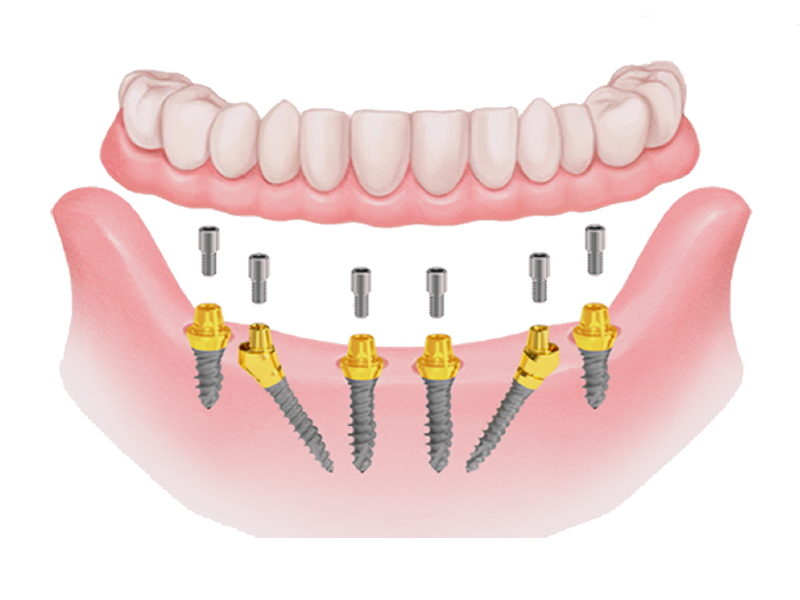

6 dental implants

6 abutments

12 temporary teeth (movable)

12 resin crowns (fixed teeth)

Another great advantage that derives from the All on 6 method is the immediate load, on the inserted implants your new fixed teeth are fixed in the same session or at most in a second sitting after a few days.

Simplicity of application

Extreme precision of implant placement

Fast, safe, painless application